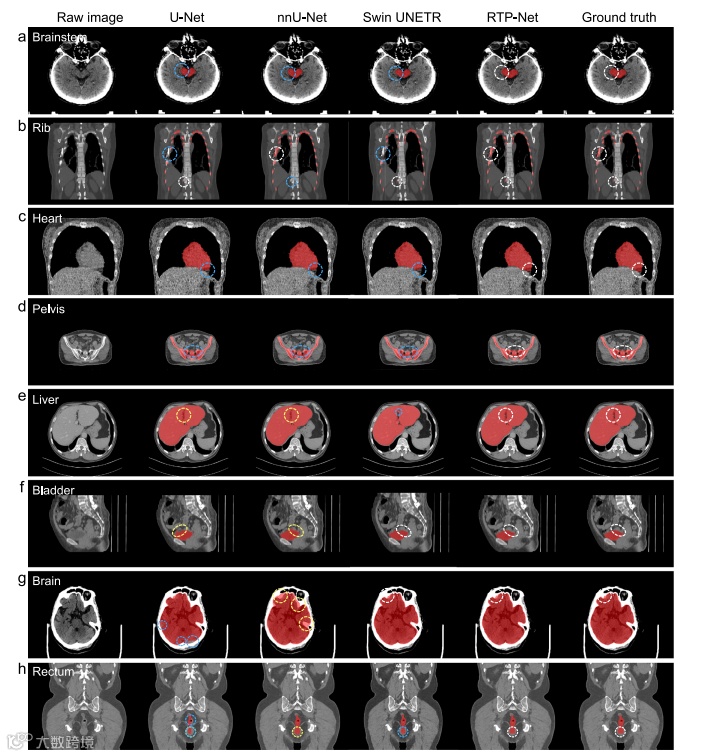

RTP-Net与U-Net/ nnU-Net/ Swin UNETR在八个关键器官上的视觉对比

本图每行展示同一器官的CT切片,依次列出四种方法结果与金标准:RTP-Net均与金标准贴合良好;U-Net与nnU-Net在脑干、肋骨、心脏、骨盆出现明显欠分割(蓝圈),在肝脏、膀胱出现过分割(黄圈);Swin UNETR在膀胱、大脑尚可,其余六器官欠分割。整体凸显RTP-Net边界的准确性与结构完整性。